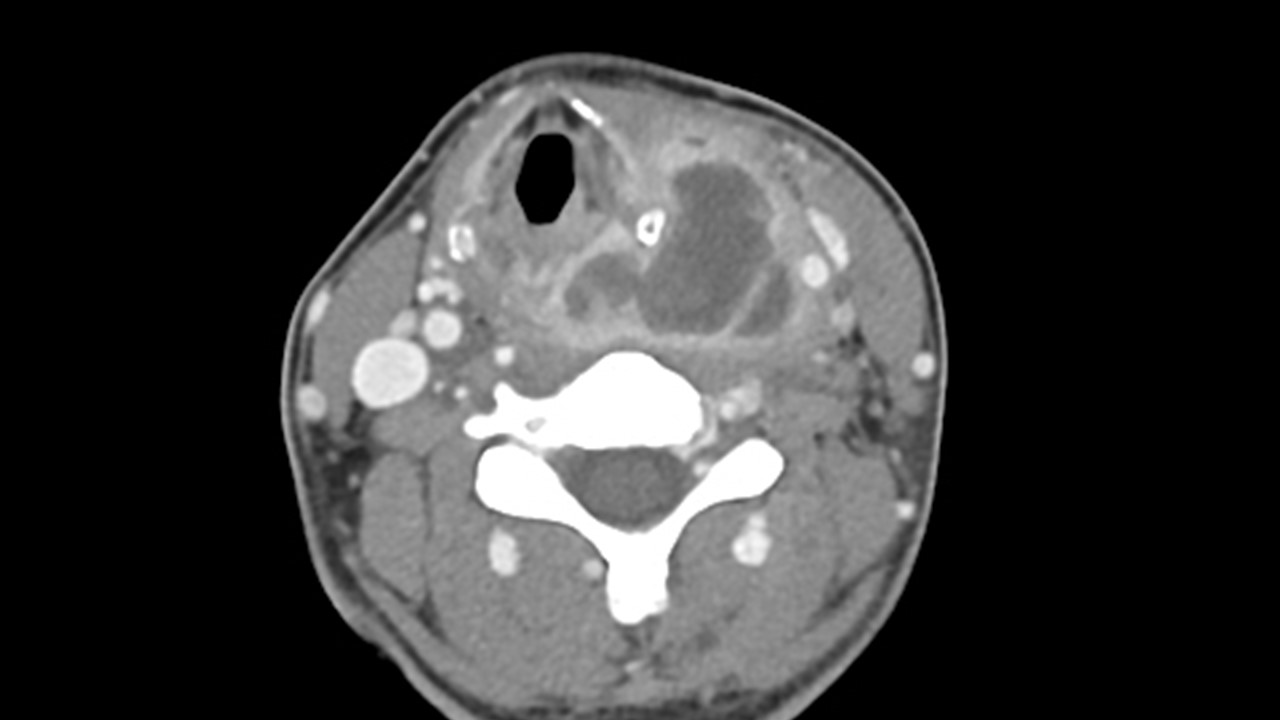

[369,] 48/F,Sore throat, neck pain

Modality

US,CT,

What is the most likely diagnosis?

[Diagnosis]

1.

Hypopharynx cancer with thyroid invasion

2.

Infected 4th branchial cleft anomaly

3.

Infected thyroglossal duct cyst

4.

Anaplastic thyroid cancer

5.

Infected 3rd branchial cleft anomaly